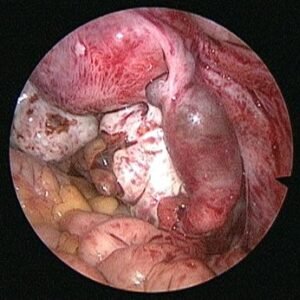

The diagnosis is also confirmed with ultrasound and blood flow studies (Doppler) during which the sac may be visualized in the region of the adnexa close to ovary. The treatment may be medical with methotrexate (chemotherapeutic agent) given either as oral medication or an injectable, depending on the combined laboratory and clinical findings. If surgical intervention is decided upon then laparoscopic surgery will be performed in most patients who are hemodynamically stable. In cases where the patient presents late with the symptoms or the pregnancy has ruptured with bleeding into the abdomen laparotomy (10%) is performed.

The affected tube is most often if not always removed after examining the opposite tube and assessing the patient’s chances of future conception. Even with one healthy tube it is possible to conceive. In our experience removal of tube almost always reduced chances of recurrence and helped improve pregnancy rates by either trying for conception with the opposite tube or with ART.